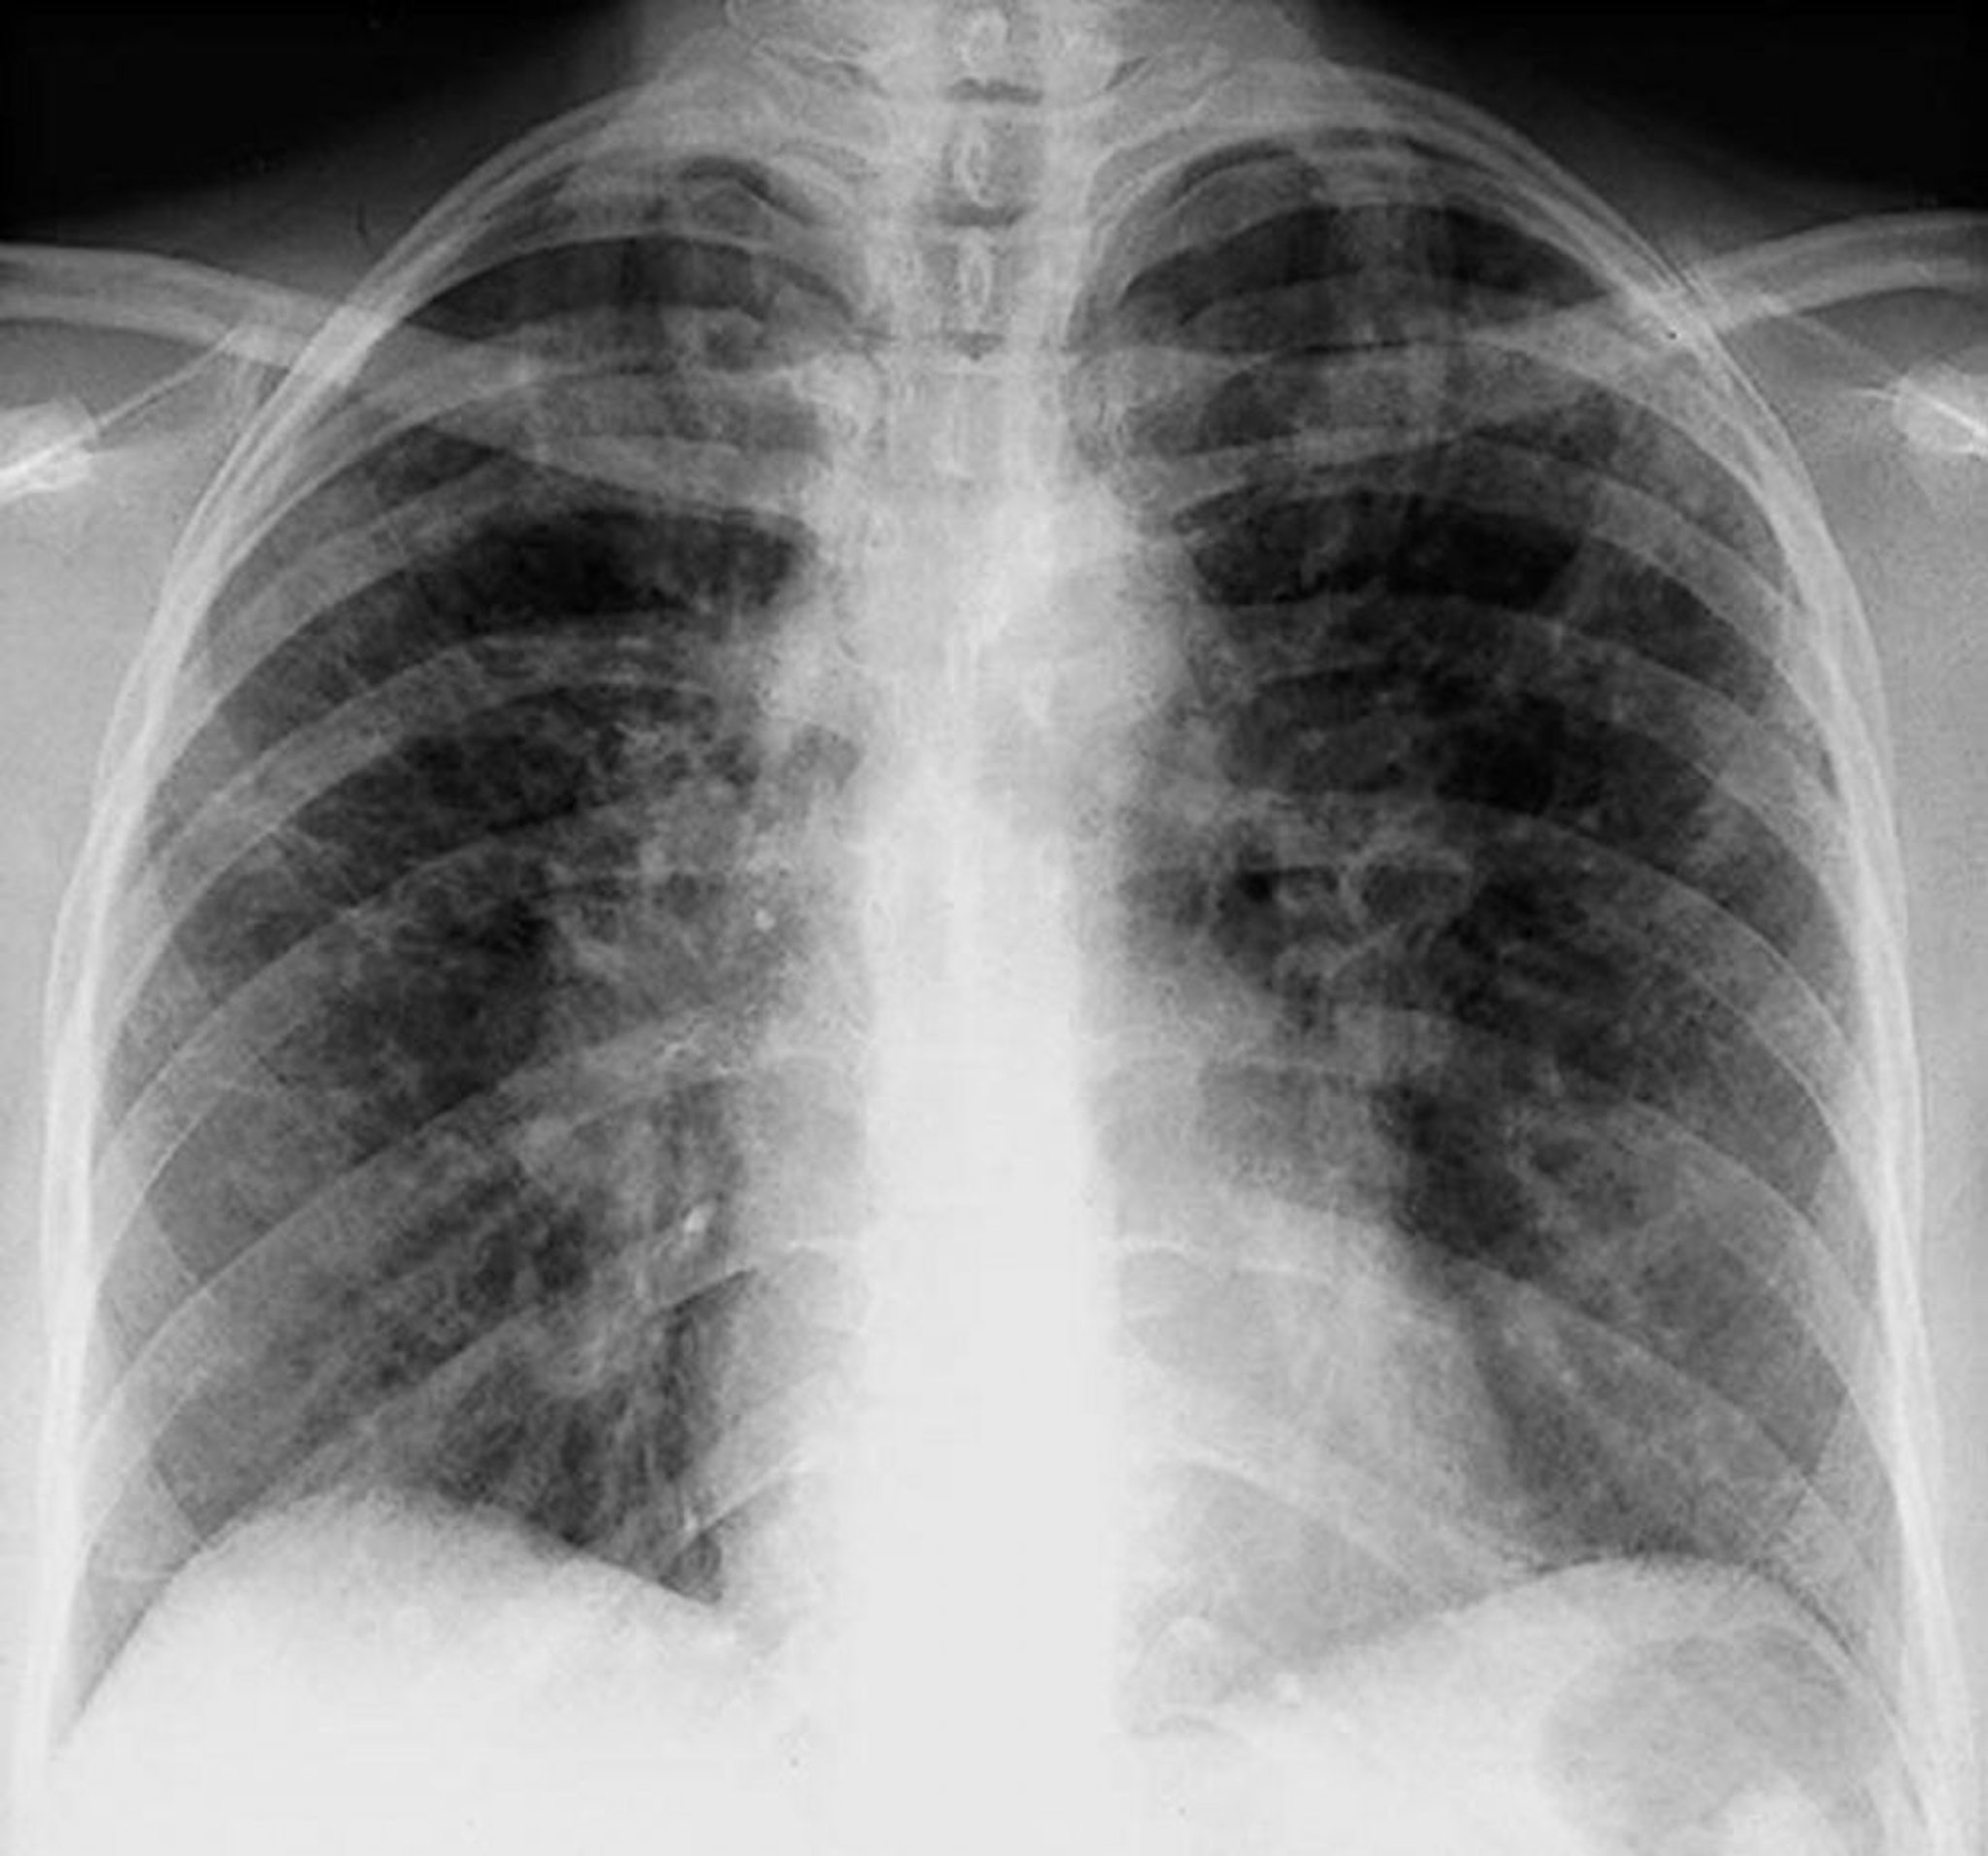

Sarcoidosis (Stage II)

Bilateral hilar adenopathy with interstitial opacities in stage II sarcoidosis.

By permission of the publisher. From Tanoue L, Elias J. In Bone's Atlas of Pulmonary and Critical Care Medicine. Edited by J Crapo. Philadelphia, Current Medicine, 2005.